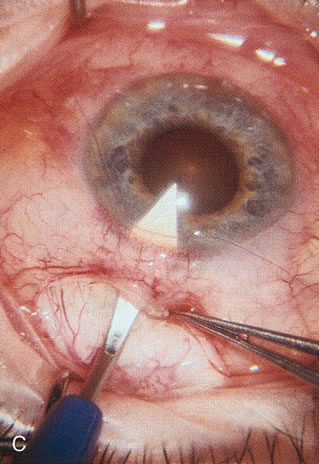

CATARACT EXTRACTION ALONE REDUCES IOP IN MOST EYES WITH ANGLE-CLOSURE GLAUCOMA

Uncomplicated cataract extraction substantially reduces IOP, along with the number of postoperative glaucoma medications in eyes with angle-closure glaucoma.146,147 When preoperative gonioscopy reveals PAS, along with adjacent areas of appositional closure, lens extraction alone in select cases may be a reasonable alternative to filtration surgery.148,149 Phacomorphic angle-closure disease due to enlargement of the lens with progressive angle crowding is eliminated following lens extraction. The width and depth of the anterior chamber angle in eyes with angle-closure glaucoma increases significantly after cataract extraction with IOL implantation and becomes similar to open-angle glaucoma and normal eyes.150,151 (Fig. 5). Combining phacoemulsification, IOL implantation, and limited goniosynechialysis is effective in the treatment of cataract and chronic angle-closure glaucoma.152 Phacoemulsification with implantation of a foldable IOL is more effective in reducing IOP and improving visual acuity than surgical peripheral iridectomy in eyes with acute angle-closure glaucoma.153

Fig. 5. Anterior chamber angle changes associated with lens extraction and PCIOL This 65-year-old Vietnamese woman has a long-standing history of chronic angle-closure glaucoma treated with laser peripheral iridectomy. The optic nerve demonstrated mild glaucomatous damage and IOP was moderately controlled on two antiglaucoma medications. The cataract was removed through temporal clear corneal phacoemulsification with foldable acrylic IOL. A. Symptomatic cataract in narrow-angle glaucoma eye with patent iridectomy. B. Intraoperative goniophotograph showing crowding of angle with increasing narrowness due to phacomorphic component. C. Intraoperative photograph showing temporal clear corneal approach with IOL in the capsular bag. D. Intraoperative goniophotograph demonstrating deepening of chamber angle following lens extraction. Proposed theories for IOP reduction following lens extraction with complete wound closure:

1. Anterior chamber deepening with improved access to trabecular meshwork

2. Increase in traction on the trabecular meshwork

3. Improved outflow facility mediated by an increase in prostaglandin release

4. Reduction in aqueous humor production

5. Atrophy of ciliary body processes

6. Goniosynechialysis due to intraoperative over deepening of AC with viscoelastic

7. Relief of undiagnosed pupil block